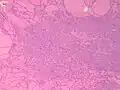

Fine-needle aspiration for cytology is generally not indicated in an autonomously functioning thyroid nodule, as the risk of malignancy is low, and it is generally difficult to distinguishing between a benign lesion and a malignant lesion in such specimens.[8] If thyroidectomy is performed, histopathology can corroborate the diagnosis. Toxic multinodular goiter more or less corresponds to diffuse or multinodular hyperplasia of the thyroid (Grave's disease also shows hyperplasia, but typically more prominent thickening of follicular linings):

- Diffuse thyroid hyperplasia typically shows variably sized follicles

- Thyroid hyperplasia with a hyperplastic nodule. It characteristically has no capsule (distinguishing it from thyroid adenoma or carcinoma).

- The follicular linings may be thickened, with papillary projections (but lack nuclear features of papillary thyroid carcinoma)

- The epithelium may also be flattened by enlarged follicles.

- It can show hypercellular or microfollicular areas. There is no surrounding capsule (in contrast, a thyroid follicular adenoma or carcinoma is generally encapsulated).

- As shown in these microfollicles, it can have mildly enlarged nuclei with mildly clumped chromatin, and clear cytoplasms, but cellular characteristics of papillary thyroid carcinoma are absent.

- Thyroid hyperplasia with a Sanderson polster, which is a group of small follicles that protrude into the lumen of a larger follicle. It should not be confused for papillary projections.

- Various forms of degeneration are typically seen, with various forms pictured.